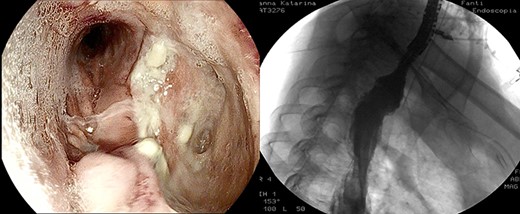

Healthy-appearing granulation tissue and progressive reduction of leak and cavity size.

Anastomotic dehiscence was conservatively treated by EVAC therapy, placing the Esosponge in pleural space via an overtube (Fig. 2).

The patient underwent 14 treatment sessions over 35 days. The leak and the cavity size progressively improved with the development of healthy-appearing granulation tissue s (Fig. 3). Inflammatory indexes and clinical conditions similarly improved. The endoscopic findings were confirmed by CT scans. Complications were not observed.